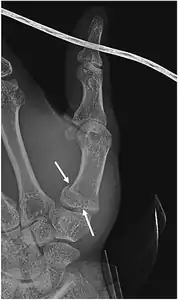

- In the most minor cases of Bennett fracture, there may be only small avulsion fractures, relatively little joint instability, and minimal subluxation of the CMC joint (less than 1 mm). In such cases, closed reduction followed by immobilization in a thumb spica cast and serial radiography may be all that is required for effective treatment.[8]

- For Bennett fractures where there is between 1 mm and 3 mm of displacement at the trapeziometacarpal joint, closed reduction and percutaneous pin fixation (CRPP) with Kirschner wires is often sufficient to ensure a satisfactory functional outcome. The wires are not employed to connect the two fracture fragments together, but rather to secure the first or second metacarpal to the trapezium.